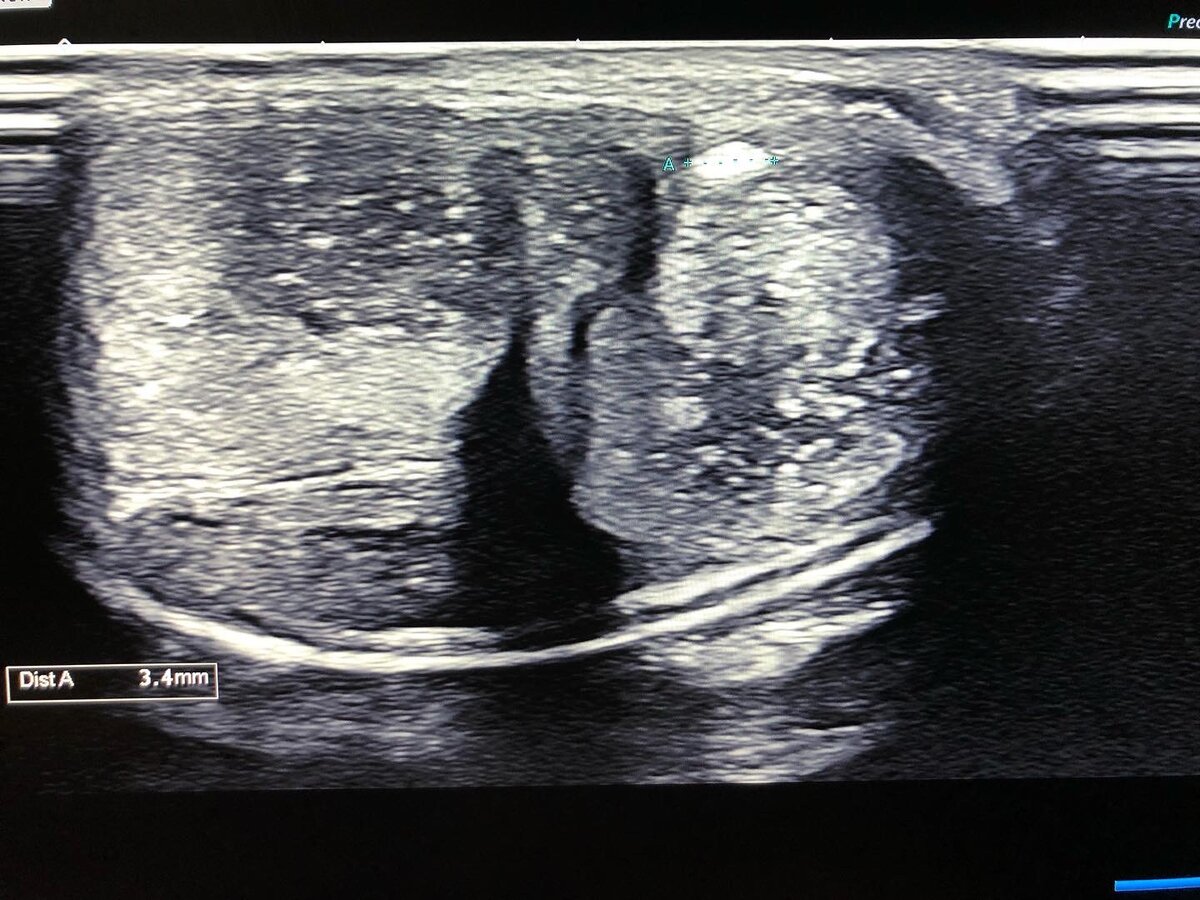

🔺Развитию веногенной ЭД способствуют нарушения в венозном кровяном русле, при которых просвет вен увеличивается.

✅Это случается при эктопическом дренировании КТ через венозные сосуды пениса, при травматических разрывах белочной оболочки, в результате чего развивается её недостаточность.

✅Веногенная ЭД часто сопутствует Болезни Пейрони и функциональной недостаточности кавернозной эректильной ткани.